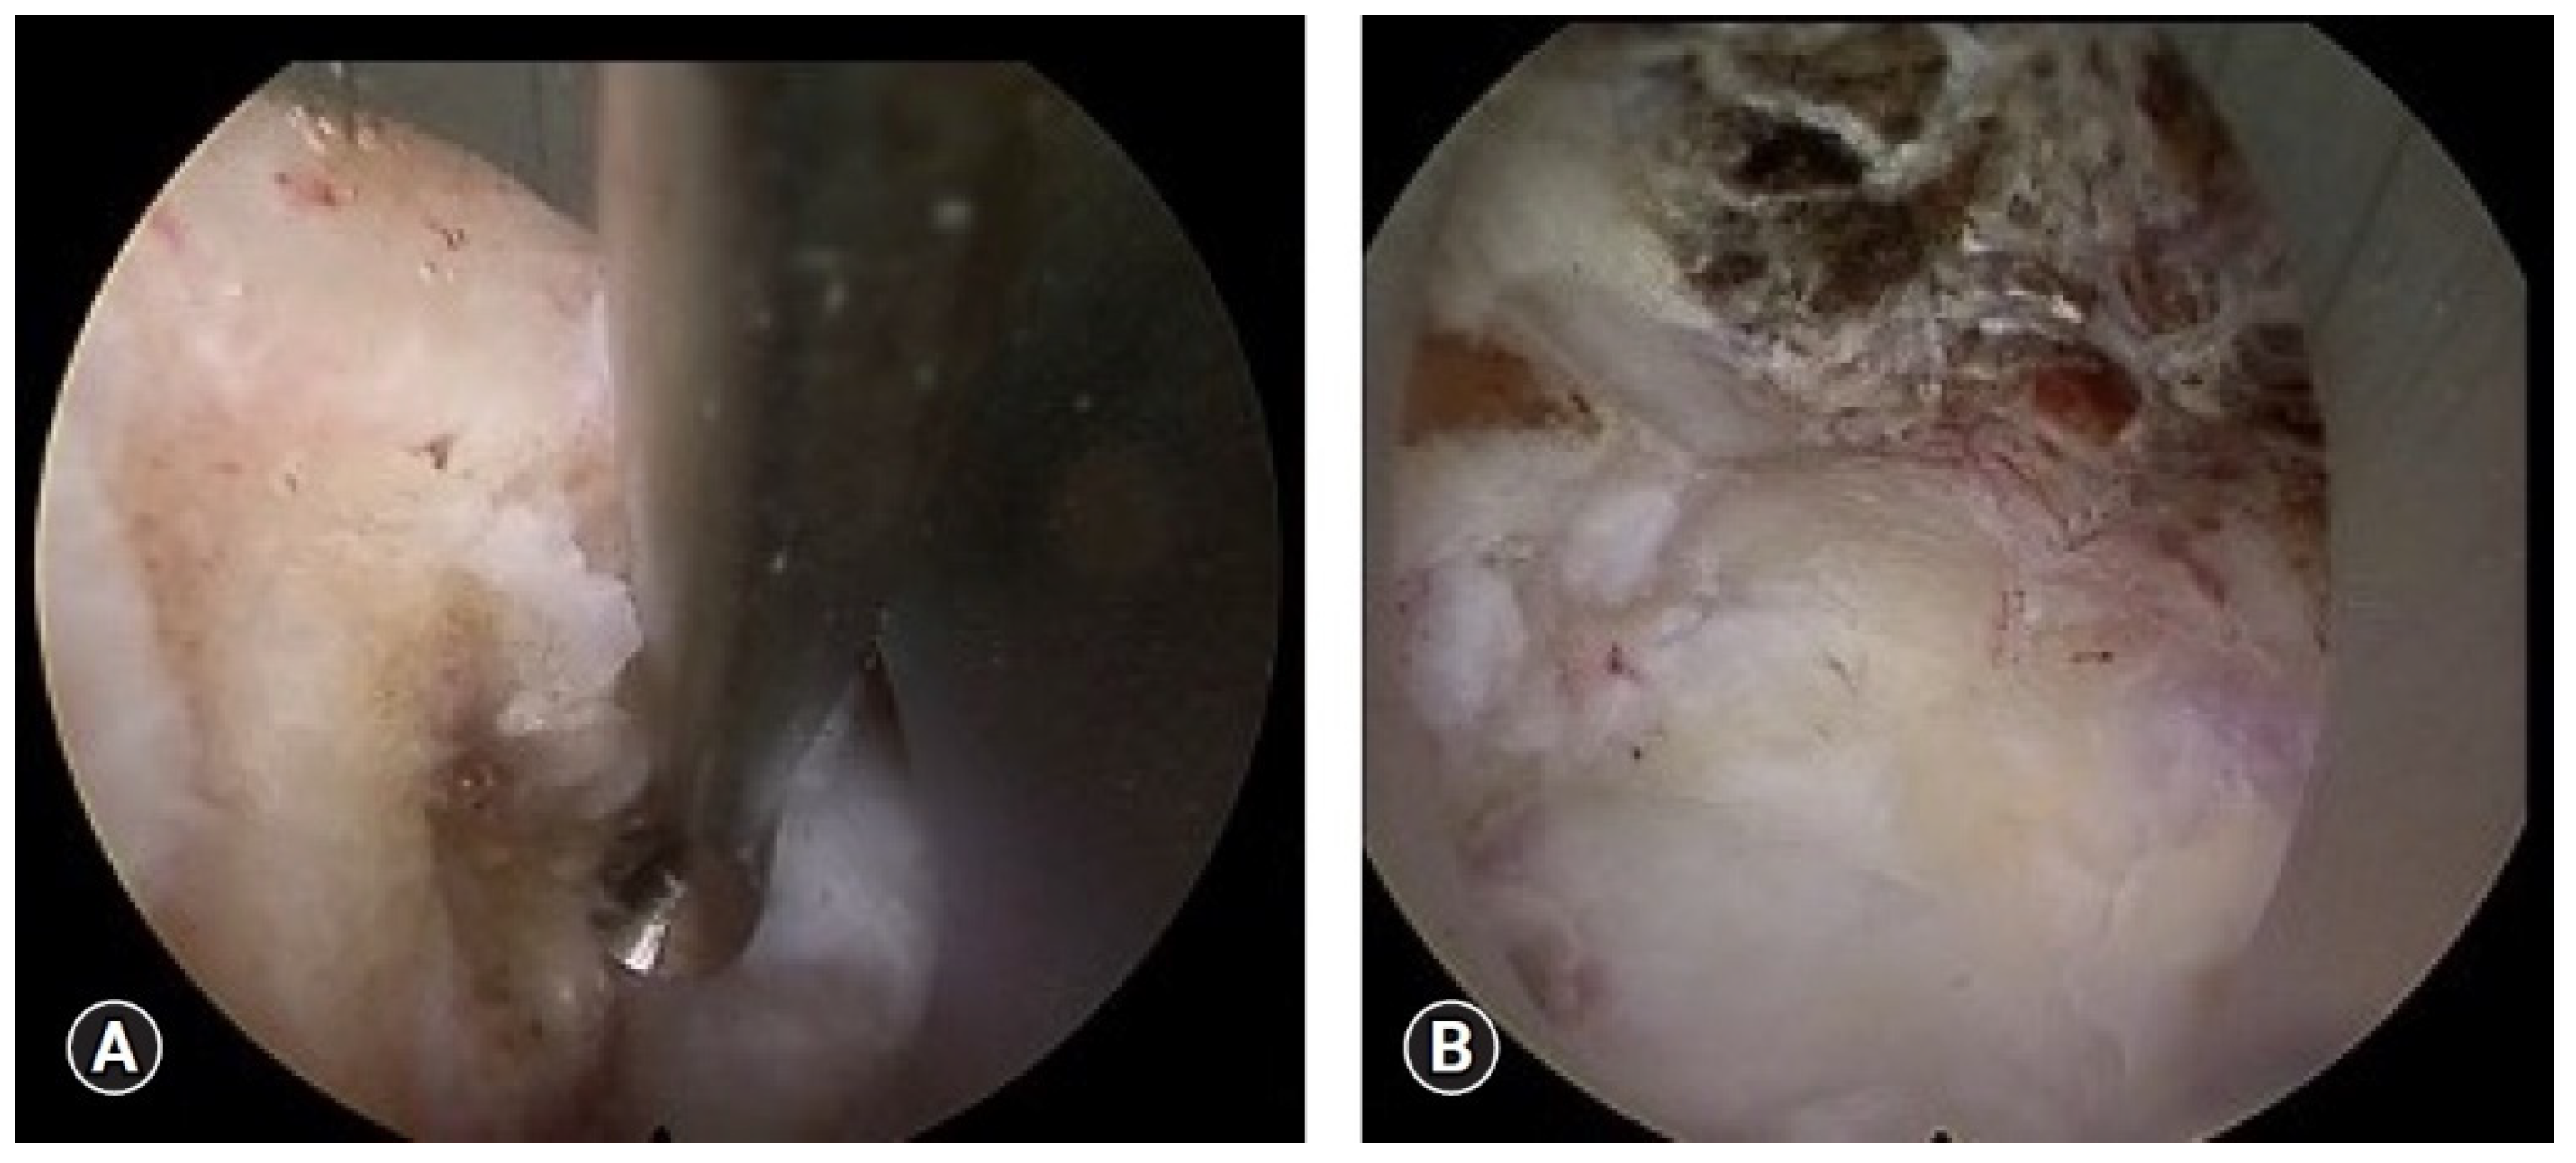

3. Transoral Cervical Approaches

- Frempong-Boadu, A.K.; Faunce, W.A.; Fessler, R.G. Endoscopically Assisted Transoral-Transpharyngeal Approach to the Craniovertebral Junction. Neurosurgery 2002, 51, S2-60–S2-66. [Google Scholar] [CrossRef]